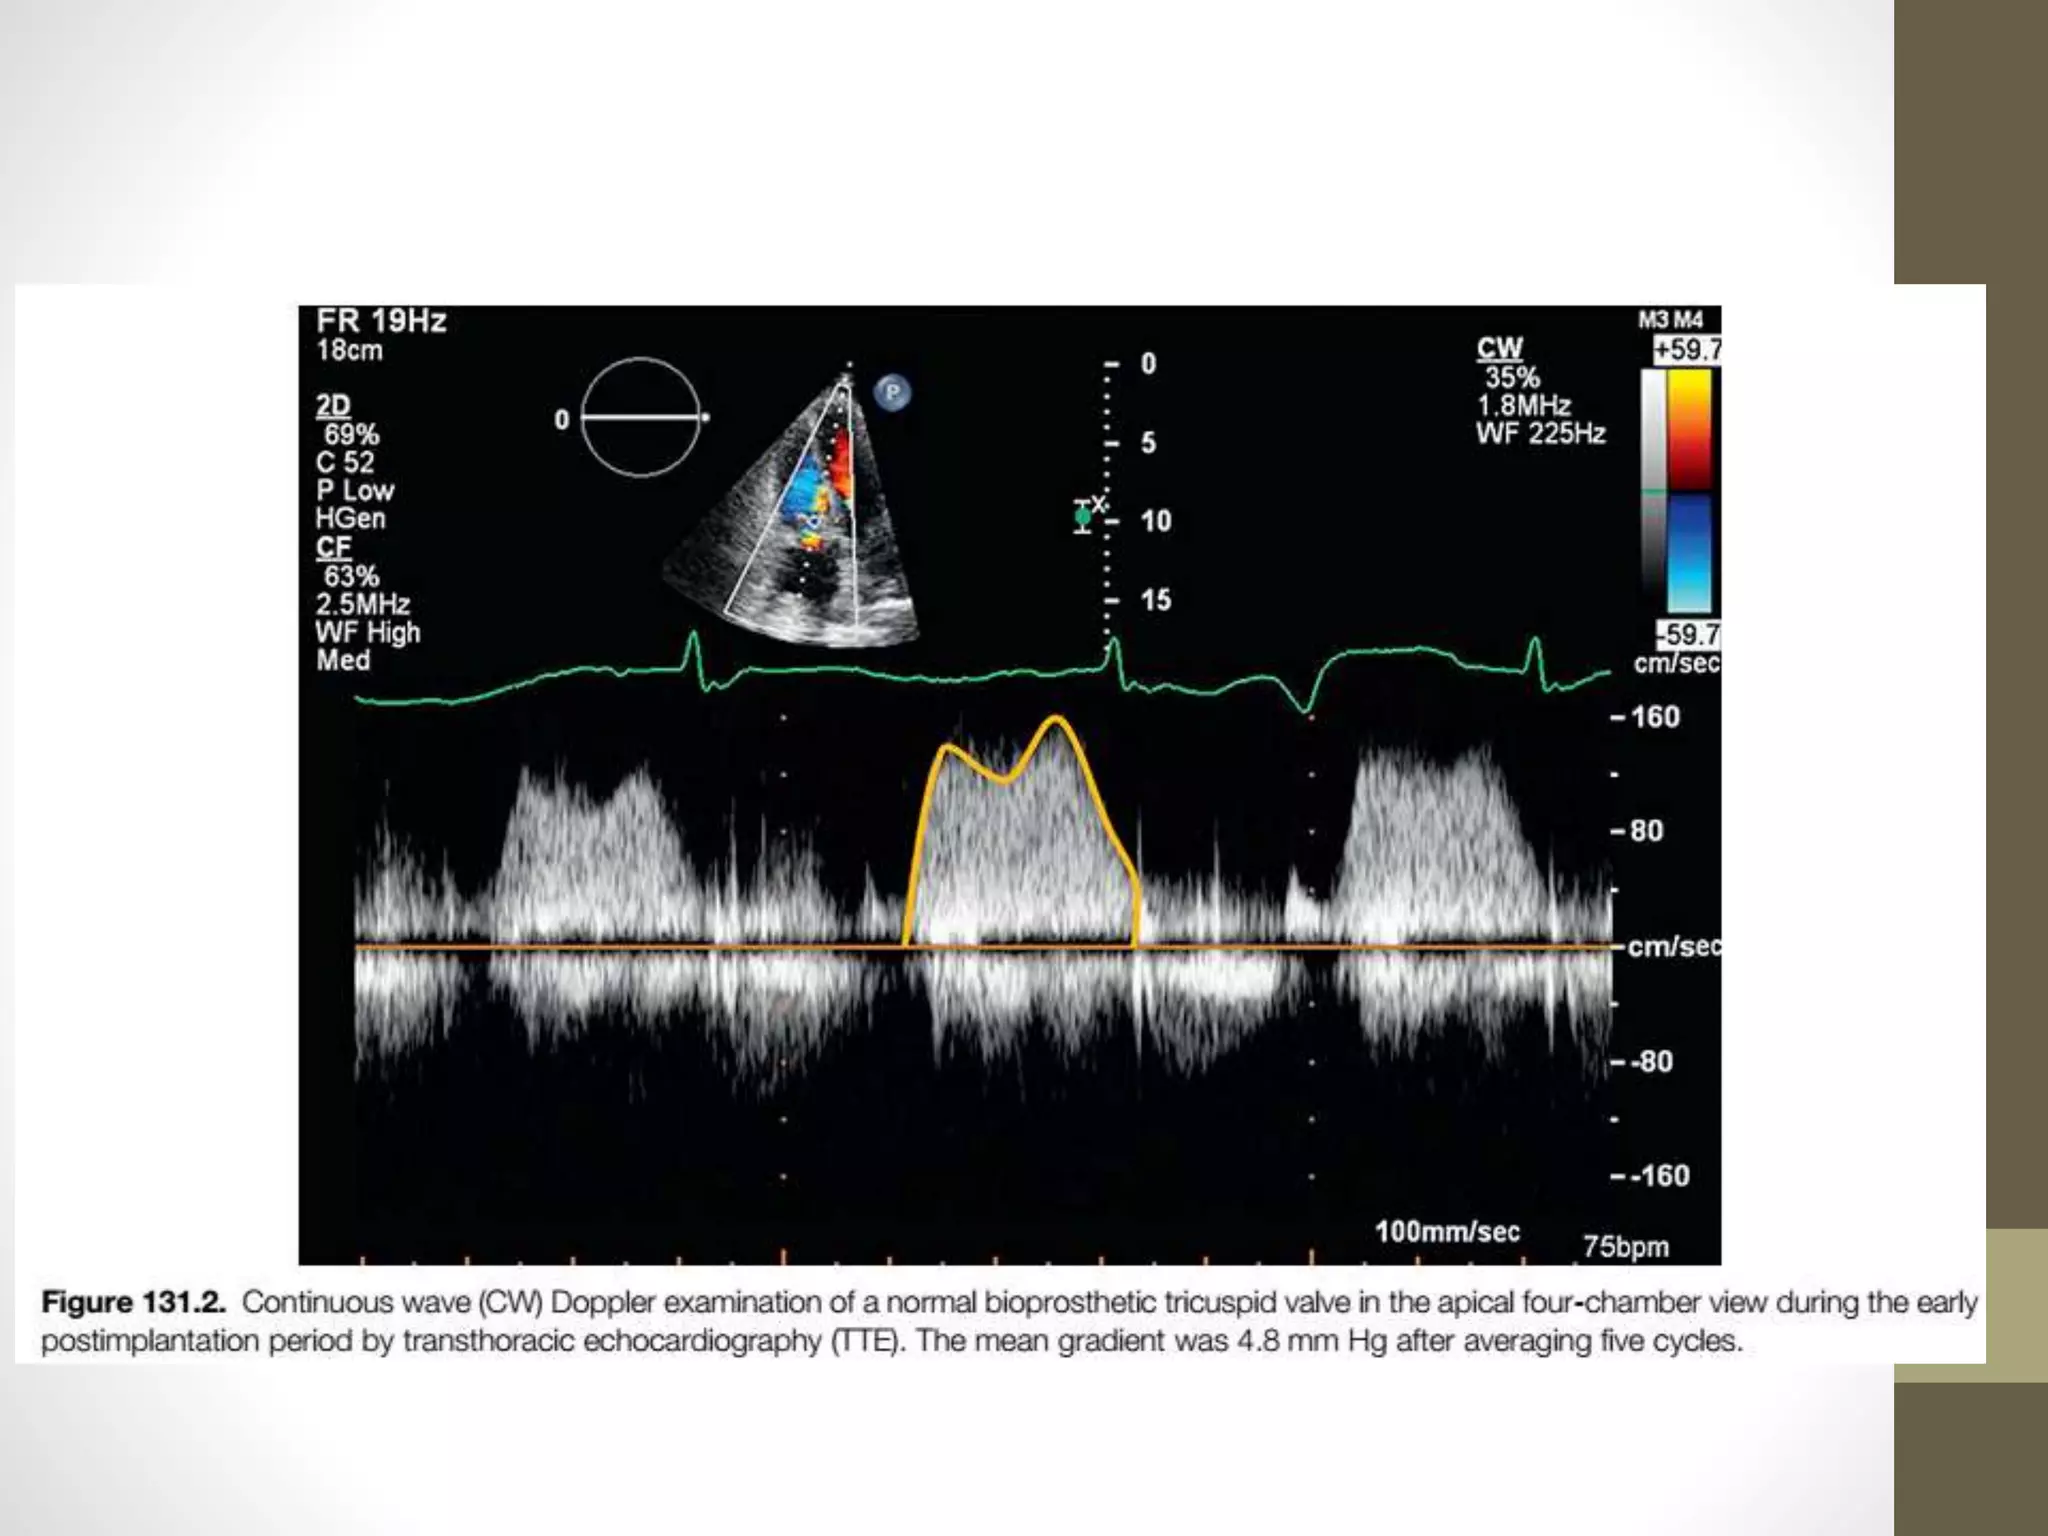

tricuspid prosthesis post implantation.

• It is important to average Doppler measurements from at

least five cardiac cycles

• because measurements may vary significantly because of

respiration in the tricuspid position.

Mean Gradient

• Recent guidelines recognize a mean gradient less than 6 mm

Hg as normal and values of 6 mm Hg or greater as suggesting

prosthetic valve stenosis.

• A recent study that included a larger number of patients with

bioprosthetic valves early after operation demonstrated that

a mean gradient greater than 9 mm Hg is highly suggestive of

tricuspid bioprosthetic valve stenosis,

• and thus further imaging with TEE should be considered in

these circumstances